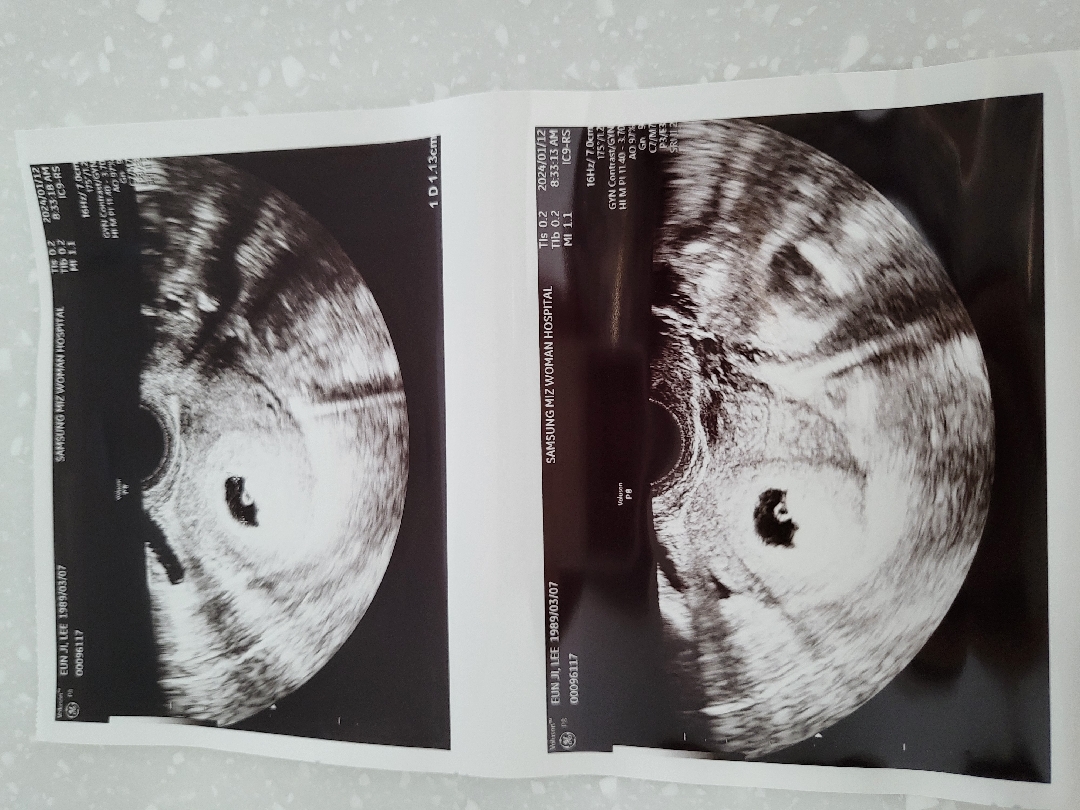

축하드려요!!!🥰🥰 왼쪽 부분에 있는 검은 덩어리가 아기집, 그 안에 작은 존재가 난황이에요 ㅎㅎ 저도 초음파 보는 법 잘 몰라서 인터넷에 엄청 쳐봤었던 기억이😂

오늘 드디어 아기집을 보고 왔어요 이제 실감이 조금은 나는듯 해욬ㅋ 근데 이거 초음파 사진 보는법 좀 알려주세요ㅠㅠ

재미로 보는 난황 위치로 성별을 알 수 있다는데 저는 중간같기도 오른쪽 같기도 한데 위치가 어디일까요?ㅋㅋ

보통 4등분해서 기준으로 보시던데 그 기준이면 약간 오른쪽 같아 보이는 걸요!!!!! 댓글에 사진을 못 넣어 아쉬운데ㅠㅠ 네이버에 “난황위치성별” 검색하니 사등분해서 왼쪽 오른쪽 보는 글이 있네요 히히 저도 잘 몰라서 방금 검색해 봤는데 요거 재밌잖아요..!? 저도 나중에 초음파 보고 한 번 봐봐야겠어요 ㅋㅋㅋㅋㅋ

큰까망이 아기집 중간에 작은 동그라미가 난황이에요

그럼 아기는 어디있어요? 그리고 난황 크기도 적당해야 된다는데 그건 어떻게 보는걸까요?ㅠ

아직 아기가 딱 안보여용 ㅎㅎ ㅠ 난황크기에 문제가 있었으면 병원에서 이야기해줬을꺼에용 ㅎㅎ그리고 난황위치에 따른 성별은 확실하진 않은것 같아요 작년에 첫찌 출산했는데 위치가 조금씩 달라지더라구요ㅠ ㅎ..

한 7-8주 쯤 되면 난황에 올챙이처럼 아기가 보일거게용